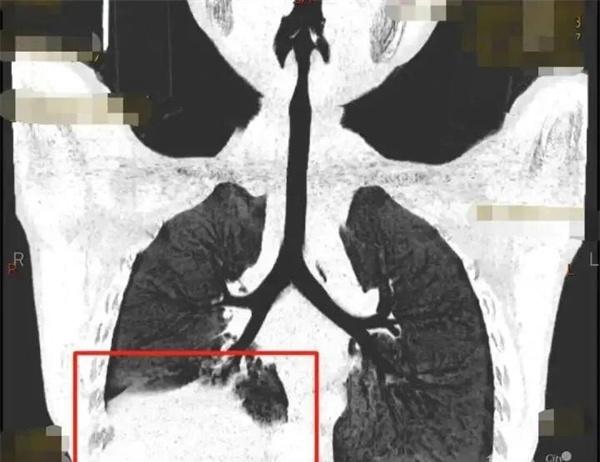

6歲小男孩發(fā)燒11天時間都不退,經(jīng)過CT檢查發(fā)現(xiàn)孩子肺部已經(jīng)有了很嚴重的感染,已經(jīng)要痰栓阻塞了,就像一根根樹枝一樣,不處理對于肺部功能會有較為嚴重的影響。之所以有痰栓阻塞,是因為有塑形性支氣管炎的患兒,在氣道炎癥的分泌物過于粘稠,長時間沒有辦法將這些分泌物咳出,就會成為膠凍狀的痰栓在支氣管內(nèi)部堵塞。

順利將碳酸全部取出后,小男孩在呼吸內(nèi)科接受了抗感染的治療以及激素的治療,肺部的感染狀態(tài),也在逐漸好轉(zhuǎn)。因為治療不夠及時的原因,這一次感染給身體也留下了無法避免的創(chuàng)傷,肺炎支原體肺炎所引起痰栓這種狀況是有的,但并不是高發(fā)的情況。如果一直高燒都不退的話,一直咳嗽且不斷的發(fā)熱在肺部,影像提示有著較為厲害的病變,不及時發(fā)現(xiàn)治療的話是很容易有痰栓形成的,具體根據(jù)孩子的病情作出判斷。